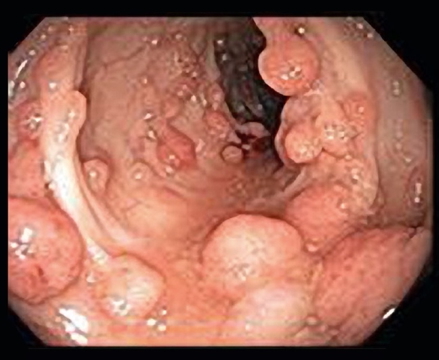

Types of Polyps

Neoplastic (10%)

- Adenomas

- Tubular (90%) – pedunculated

- Tubulovillous (<10%) – mixed pattern

- Villous (<1%) – sessile, highest malignancy risk

Familial Adenomatous Polyposis (FAP)

- Autosomal dominant; thousands of adenomas

- 100% cancer risk if untreated

- Colonoscopy + Polypectomy (for diagnosis and prevention)